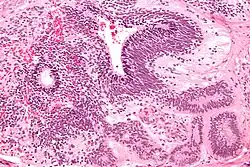

| Micrograph of the primitive neuroepithelium of an immature teratoma. H&E stain. | |

An immature teratoma contains varying compositions of adult and embryonic tissue. The most common embryonic component identified in immature teratomas is the neuroectoderm.[19] Occasionally, tumors may present neuroepithelium that resemble neuroblasts.[19] Tumors may also present embryonic components such as immature cartilage and skeletal muscle of mesodermal origin.[19] Immature teratomas composed of embryonic endodermal derivatives are rare.[19]

Often a mature cystic teratoma is misdiagnosed as its immature counterpart due to the misinterpretation of mature neural tissue as immature.[20] While mature neural cells have nuclei with uniformly dense chromatin and neither exhibit apoptotic or mitotic activity, immature neural cells have nuclei with vesicular chromatin and exhibit both apoptotic and mitotic activity.[20] A recent study has identified the use of Oct-4 as a reliable biomarker for the diagnosis of highly malignant cases of immature teratomas.[21]